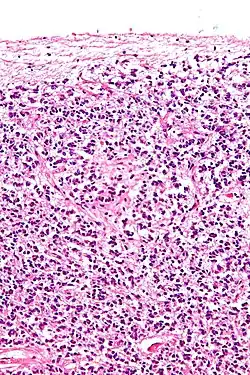

Cross-section of pineal gland displaying pinealocytes and other cells

Pinealocytes are the main cells contained in the pineal gland, located behind the third ventricle and between the two hemispheres of the brain. The primary function of the pinealocytes is the secretion of the hormone melatonin, important in the regulation of circadian rhythms.[1] In humans, the suprachiasmatic nucleus of the hypothalamus communicates the message of darkness to the pinealocytes, and as a result, controls the day and night cycle.[2] It has been suggested that pinealocytes are derived from photoreceptor cells.[3][4] Research has also shown the decline in the number of pinealocytes by way of apoptosis as the age of the organism increases.[5] There are two different types of pinealocytes, type I and type II, which have been classified based on certain properties including shape, presence or absence of infolding of the nuclear envelope, and composition of the cytoplasm.